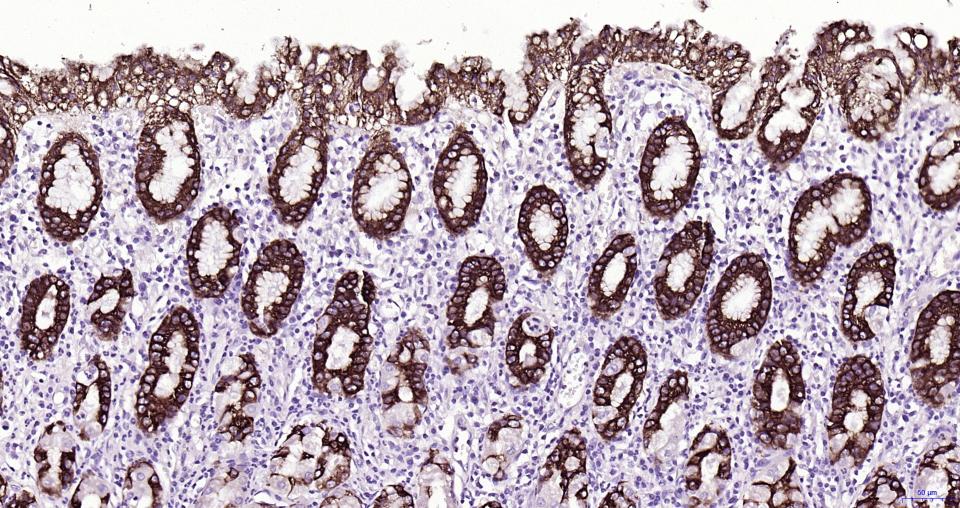

Paraformaldehyde-fixed, paraffin embedded Human Stomch; Antigen retrieval by boiling in sodium citrate buffer (pH6.0) for 15 min; Antibody incubation with MUC5AC Monoclonal Antibody, Unconjugated(bsm-61467R) at 1:200 overnight at 4°C, followed by conjugation to the SP Kit(Rabbit, SP-0023) and DAB (C-0010) staining.